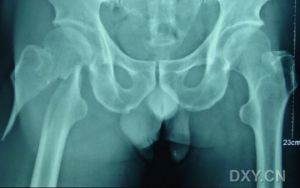

股骨粗隆間骨折股骨粗隆間骨折又名股骨轉子間骨折,是老年人常見的骨折。隨著社會的老齡化,人均壽命的延長,骨質疏鬆人數的增加,老年人發生股骨粗隆間骨折的機率呈上升趨勢。

股骨粗隆間骨折由間接暴力和直接暴力損傷產生。老年患者的股骨粗隆間骨折,多為直接外力如跌倒所致。因常伴有不同程度的骨質疏鬆,故易造成嚴重的粉碎性骨折。

股骨粗隆間骨折的分型很多,目前公認並得以套用的有以下十種:Evans分型(1949),BoydGriffin分型(1949),Ramadier分型(1956),DecoulxLavarde分型(1969),Ender分型(1970),Tronzo分型(1973),Jensen分型(1975),Deburge分型(1976),Briot分型(1980),AO分型(1981)。所有分型可歸為兩類:a)解剖學描述(Evans;Ramadier;DecoulxLavarde);b)提示預後(Tronzo;Ender;Jensen改良的Evans分型)。

任何骨折分型必須套用簡便,並能指導治療,同時提示預後才能具有臨床意義。就股骨粗隆間骨折分型而言,能夠對於骨折的穩定性及復位、固定之後骨折部位能否耐受生理應力做出判斷尤為重要。AO分型,Evans分型,Jensen分型和BoydGriffin分型為大家熟知並得以廣泛套用。現介紹如下。

股骨粗隆間骨折1949年Boyd和Griffin將股骨粗隆間骨折分為四型,包括了從股骨頸的關節囊以外部分至小粗隆下方5cm的所有骨折。

Ⅰ型:同大粗隆至小粗隆沿著粗隆間線所發生的骨折,穩定無移位,沒有粉碎,復位簡單(占21%)。

Ⅱ型:骨折位於粗隆間線,同時伴有皮質骨的多處骨折,為粉碎性骨折,伴有移位,復位較困難,一旦復位可獲得穩定。其中有一種特殊骨折——粗隆間前後線型骨折,骨折線只能在側位片上看到(占36%)。

Ⅲ型:基本屬於粗隆下骨折,至少有一骨折線橫過近端股骨幹小粗隆或小粗隆以遠部位,有大的後內側粉碎區域,並且不穩定,復位比較困難,手術期、恢復期併發症較多(占28%)。

Ⅳ型:粗隆區和近端股骨幹至少兩個平面出現骨折,股骨幹多呈螺鏇形斜形或蝶形骨折,骨折包括粗隆下部分,不穩定。無論選擇哪一種分型,在術前對於骨折的穩定性作出判斷十分重要。股骨粗隆間骨折穩定與否取決於兩個因素:a)內側弓的完整性(小粗隆是否累及);b)後側皮質的粉碎程度(大粗隆粉碎程度)。